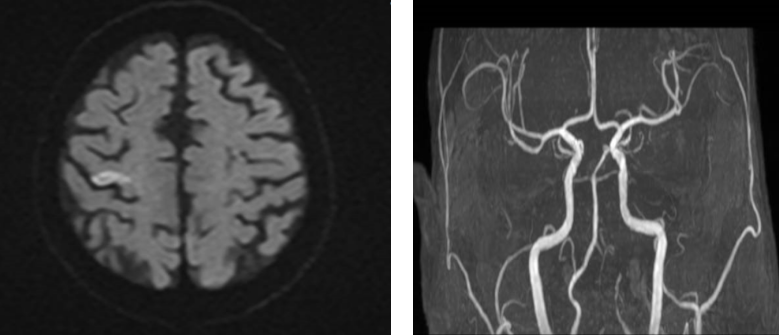

入院后,医院立即启动脑卒中绿色通道,神经内科医生全程陪同,争分夺秒完成检查。急诊头颅CT首先排除了脑出血风险,随后颅脑磁共振提示右侧额叶存在新鲜梗死灶,进一步血管评估显示患者左侧椎动脉及双侧大脑后、中动脉远端分支存在动脉粥样硬化改变,右侧大脑后动脉P3段局限性狭窄,属于典型的急性缺血性脑卒中。